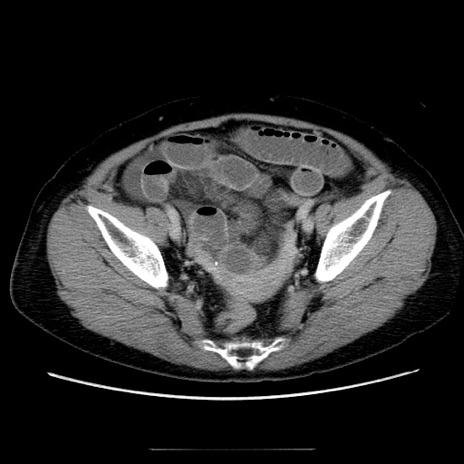

症例5(横断像)

【症例】70歳代女性

【主訴】お腹が張る

【現病歴】1週間くらい前から腹部膨満の自覚あり。昨日夜から増悪したため、本日救急外来受診。

【身体所見】意識清明、BT 36.5℃、BP 165/106mmHg、HR 80bpm、SpO2 98%、腹部:膨満、軟、自発痛・圧痛なし、触診にて不快感あり、腸蠕動音:減弱

【データ】WBC 12600、CRP 1.04